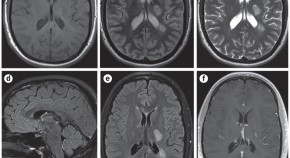

Myelin oligodendrocyte glycoprotein antibody-associated disease is an immune-mediated demyelinating disease that is distinct from multiple sclerosis but shares some of its characteristics. This Expert Recommendation, based on a Magnetic Resonance Imaging in MS workshop, proposes a diagnostic algorithm for the differential diagnosis of myelin oligodendrocyte glycoprotein antibody-associated disease and multiple sclerosis, using serological, imaging and clinical features.